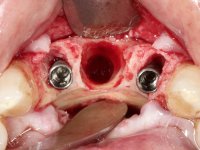

Após estudo imagiológico foi planificada a colocação de dois implantes de 3.3 mm de diâmetro e 10 mm de comprimento. No dia da cirurgia foram extraídos os dentes 42 e 32 e removido o implante. Os implantes foram colocados na zona dos alvéolos tendo o cuidado de lingualizar um pouco o seu posicionamento. Foi feita uma impressão pela técnica de moldeira aberta com o retalho aberto para a confeção da ponte provisória imediata. Enquanto a impressão foi para o laboratório, foram colocados parafusos de cicatrização altos e feita a sutura da ferida cirúrgica. A paciente esperou 2 horas na sala de espera enquanto no laboratório era confecionada a ponte provisória. A ponte provisória imediata aparafusada foi colocada e o seu assentamento controlado imagiologicmente. Passados 3 meses foi realizada a impressão definitiva com uma técnica de moldeira aberta. Nessa consulta aproveitamos para polir a ponte provisória com taças de borracha para que os tecidos moles pudessem maturar em melhores condições. Foi feita a recolha de informação para caracterizar da melhor forma a estrutura monolítica em Zr. Foram utilizadas guias de cor para a cerâmica de tonalidade coronária e gengival. No laboratório foi confecionada uma ponte em Zr. aparafusada que foi cuidadosamente caracterizada. Após aprovação pela paciente foi colocada definitivamente em boca. O aperto foi feito com uma chave dinâmica com 35 N de torque. Os orifícios foram tapados com teflon e obturados com resina composta.